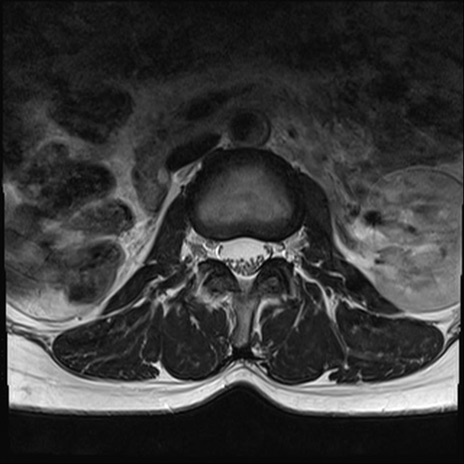

【整形】TIPS症例4 腰椎MRI T2WI(横断像)

腰椎MRI

横断像と矢状断像